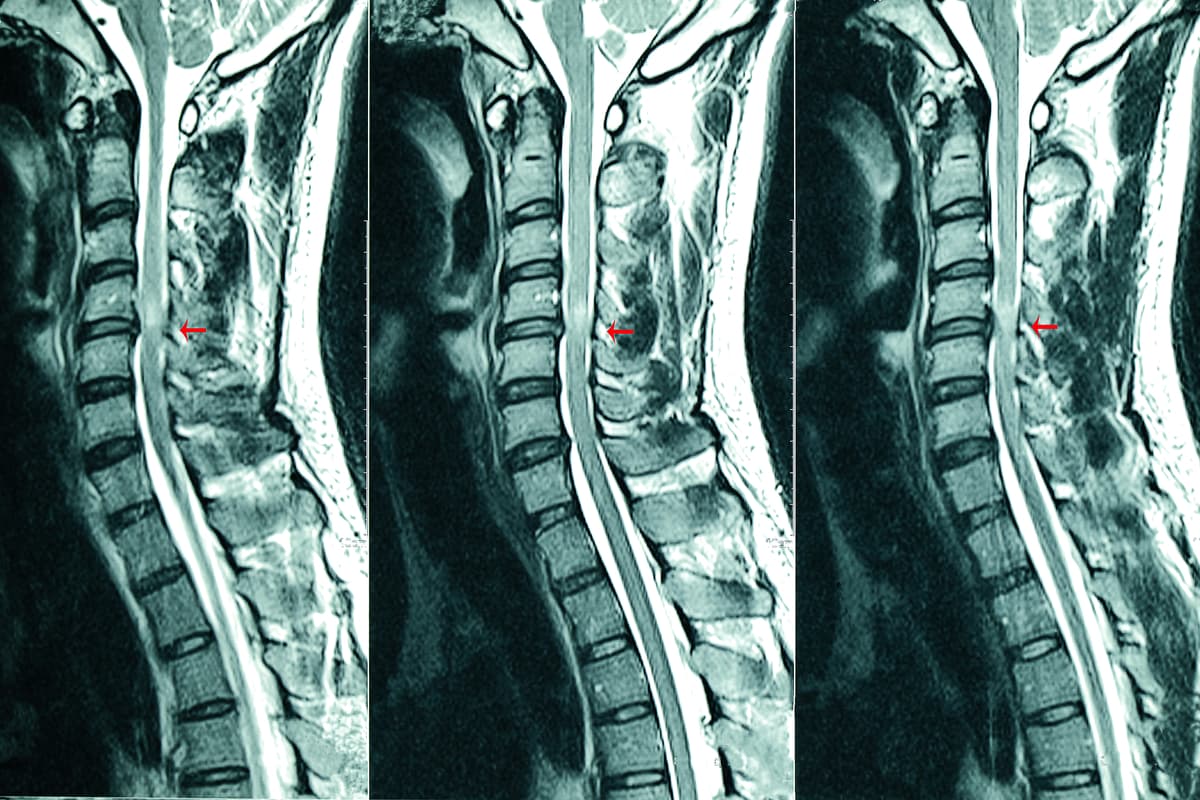

De acuerdo con la Organización Mundial de la Salud (OMS), la espina bífida es una malformación congénita que aparece durante las primeras semanas del embarazo: la columna vertebral que protege a la médula espinal no se desarrolla de manera normal.

A esta afectación se le conoce como uno de los más comunes Defectos del Tubo Neural ( DTN) y puede aparecer cuando, en cualquier tramo de la de la columna vertebral, el tubo Neural no se cierra por completo.

Al no formarse de manera correcta la espina dorsal, tanto las vértebras como la duramadre (la membrana más externa y resistente que cubre la médula espinal) provocan una protuberancia en la que se acumula una cantidad excesiva de líquido cefalorraquídeo.